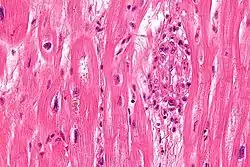

S. pyogenes has a cell wall composed of branched polymers which sometimes contain M protein, a virulence factor that is highly antigenic. The antibodies which the immune system generates against the M protein may cross-react with heart muscle cell protein myosin,[15] heart muscle glycogen and smooth muscle cells of arteries, inducing cytokine release and tissue destruction. However, the only proven cross-reaction is with perivascular connective tissue. This inflammation occurs through direct attachment of complement and Fc receptor-mediated recruitment of neutrophils and macrophages. Characteristic Aschoff bodies, composed of swollen eosinophilic collagen surrounded by lymphocytes and macrophages, can be seen on light microscopy. The larger macrophages may become Anitschkow cells or Aschoff giant cells. Rheumatic valvular lesions may also involve a cell-mediated immunity reaction as these lesions predominantly contain T-helper cells and macrophages.[16]

In rheumatic fever, these lesions can be found in any layer of the heart, causing different types of carditis. The inflammation may cause a serofibrinous pericardial exudate described as "bread-and-butter" pericarditis, which usually resolves without sequelae. Involvement of the endocardium typically results in fibrinoid necrosis and wart formation along the lines of closure of the left-sided heart valves. Warty projections arise from the deposition, while subendocardial lesions may induce irregular thickenings called MacCallum plaques.

Chronic rheumatic heart disease (RHD) is characterized by repeated inflammation with fibrinous repair. The cardinal anatomic changes of the valve include leaflet thickening, commissural fusion, and shortening and thickening of the tendinous cords.[16] It is caused by an autoimmune reaction to Group A β-hemolytic streptococci (GAS) that results in valvular damage.[17] Fibrosis and scarring of valve leaflets, commissures and cusps leads to abnormalities that can result in valve stenosis or regurgitation.[18] The inflammation caused by rheumatic fever, usually during childhood, is referred to as rheumatic valvulitis. About half of patients with rheumatic fever develop inflammation involving valvular endothelium.[19] The majority of morbidity and mortality associated with rheumatic fever is caused by its destructive effects on cardiac valve tissue.[18] The complicated pathogenesis of RHD is not fully understood, though it has been observed to use molecular mimicry via group A streptococci carbohydrates and genetic predisposition involving HLA Class II genes that trigger autoimmune reactions.[20]